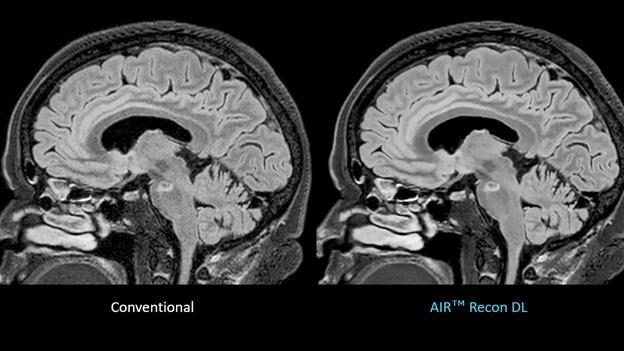

GE Healthcare has received FDA 510(k) clearance of its AIR Recon DL for 3D and motion-insensitive PROPELLER imaging sequences.

Loannis Panagiotelis, chief marketing officer for MR at GE HealthCare, said that his company has endeavored to address patient access to medical imaging and system productivity by increasing adoption of technological solutions that enable shorter scan times and sharpen image technology. AIR Recon DL, a deep-learning-based image reconstruction algorithm, removes image noise and artifacts from scans, leveraging raw image data to scan patients faster without compromising image quality.

Panagiotelis claimed the technology, which has been years in development, can sharpen images by as much as 60 percent and cut scan time in half.

Panagiotelis said. “We made [AIR Recon DL] available for all our systems – entry-level, mainstream, higher, new systems, legacy systems – and for all anatomies. That has been a grand success.”

Panagiotelis said that the improvements to throughput and efficacy of imaging that AIR Recon DL supports have expanded the reach of MR into studies that formerly were believed to be too complicated or time-consuming for the modality, including prostate screening, musculoskeletal imaging, and gerontological studies.

“It’s become simple and accurate, and that’s why this is taking off,” he said. “It becomes easy for the people to go and have these examinations. We believe it is impactful, but at the same time we are not compromising the procedure. The sharpness of these images is increasing because of the ability to combine

To date, GE HealthCare has sold more than 3,000 AIR Recon DL licenses, and installed some 2,000 systems; as of December 2022, the technology already had been used to scan about 5.5 million patients. With that level of adoption, Panagiotelis believes more patients will benefit from its advantages sufficient to address scanning backlogs, patient discomfort in the imaging suite, and even help make radiologists more comfortable during reads.

“We made sure that as many people as possible can benefit,”

studies with new types of contrast without compromising the overall duration of the scan.”

Taken together, the myriad technological advances that work to improve operational efficiency, simplify ease of use of the imaging systems, reduce acquisition time, and enhance workflow “all brings the costs down,” Panagiotelis said. “We go over this process multiple times a year, collect customer feedback, and try to define our products to meet their needs. There are different customer segments, but increasing patient access, clarity of scans — everybody needs these things.”

GE Healthcare states that 3D imaging provides for more clinical efficiency, allowing radiologists to eliminate the need for multiple 2D acquisitions—potentially leading to faster diagnosis.